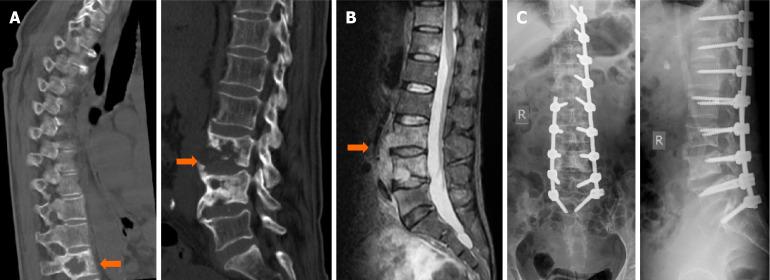

微创前路病灶清除联合后路固定治疗腰椎结核

Treatment of lumbar tuberculosis with minimally invasive anterior lesion clearance combined with posterior fixation.

Spinal tuberculosis, a destructive extrapulmonary form, often causes severe deformity and neurological deficits. Surgical intervention aims to debride lesions, reconstruct stability, and correct deformities. This study evaluates a combined posterior fixation and minimally invasive anterior approach for lumbar tuberculosis.

To evaluate the clinical outcomes and radiological parameters of posterior internal fixation combined with minimally invasive anterior lesion clearance and bone graft fusion for the treatment of lumbar tuberculosis.

Clinical data from 24 patients with lumbar tuberculosis who underwent posterior pedicle screw fixation combined with minimally invasive anterior lesion clearance were analyzed. The Cobb angle, visual analog scale (VAS) score, and Frankel classification were statistically assessed preoperatively and postoperatively. Complications and bone graft fusion were also recorded.

Wounds healed in the first stage in 22 patients; one patient developed a posterior incisional sinus tract, and one experienced postoperative tuberculosis recurrence. At the final follow-up, according to the Frankel classification, there were 1, 2, and 21 cases classified as grade C, grade D, and grade E, respectively. By the last follow-up, the Cobb angle, VAS score, and erythrocyte sedimentation rate had all decreased. Both X-ray and computed tomography images confirmed bone healing. The fusion time ranged from 3 to 9 months, with an average of 5.2 months.

Posterior pedicle screw fixation combined with minimally invasive anterior lesion clearance is an effective and safe treatment for lumbar tuberculosis.